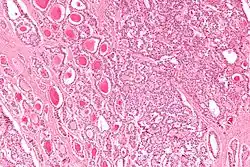

| Micrograph of a strumal carcinoid. H&E stain. |

The strumal carcinoid is a type of monodermal teratoma with histomorphologic features of (1) the thyroid gland and (2) a neuroendocrine tumour (carcinoid).[1][2]